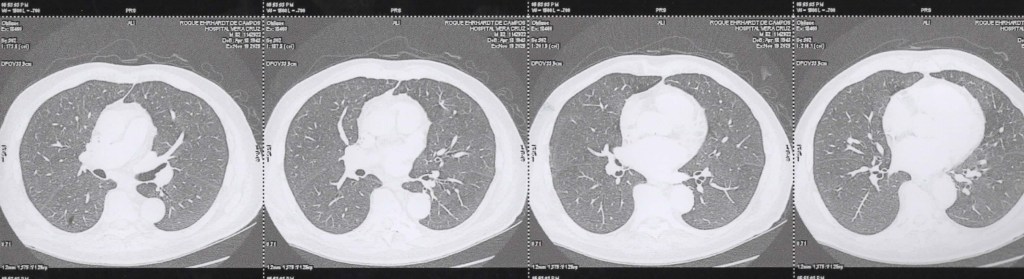

TCM Torax 19 11 2025 Axial janela pulmonar

TCM Torax 19 11 2025 Axial janela pulmonar cortes inferiores